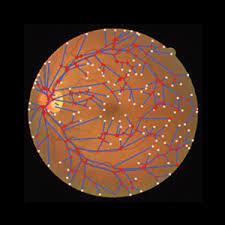

类别标签总数 = 5 图像总数 = 2750 1. 健康(非 DR) = 1000 2. 轻度 DR = 370 3. 中度 DR = 900 4. 增殖性 DR = 290 5. 严重 DR = 190 DR:糖尿病视网膜病变

类别标签总数 = 5

图像总数 = 2750

1. 健康(非 DR) = 1000

2. 轻度 DR = 370

3. 中度 DR = 900

4. 增殖性 DR = 290

5. 严重 DR = 190

DR:糖尿病视网膜病变